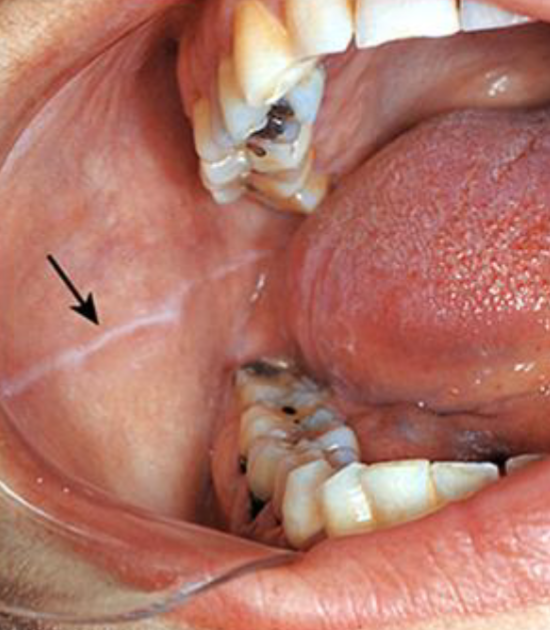

leukoedema

diffuse, gray-white, milky lesions on bilateral mucosa

disappears when stretched

how is leukoedema diagnosed